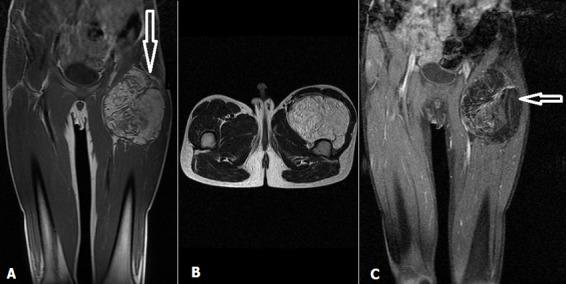

Lipoblastoma is a relatively rare benign tumor. It derives from embryonic white fat cells. It almost exclusively affects children less than 3 years of age. We report a case of lipoblastoma of the left thigh detected in an older child (11 years) and a literature review. Diagnosis was based on histology while surgical treatment was based on total resection of the mass. The postoperative course was simple with a follow-up period of 9 months.

脂肪母细胞瘤是一种相对罕见的良性肿瘤。它起源于胚胎白色脂肪细胞。几乎仅发生于3岁以下儿童。我们报告1例在大龄儿童(11岁)中发现的左大腿脂肪母细胞瘤病例并进行文献复习。诊断基于组织学检查,而手术治疗基于肿物的完整切除。术后过程顺利,随访期9个月。